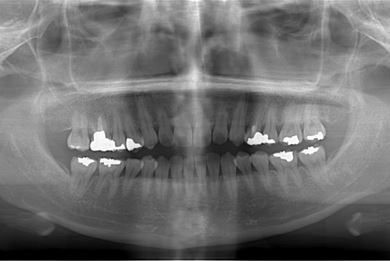

| 性別/年齢 | 女性 / 34歳 | ||||||||||||||||||||||||||||||||

| 主訴 | 以前虫歯を治療して金属を入れたところが、再び虫歯になったのか、軽くしみたり違和感がある。 | ||||||||||||||||||||||||||||||||

| 治療方針 | セラミック治療にて、審美的回復を行う。 | ||||||||||||||||||||||||||||||||

| 治療内容 | メタルボンドセラミッククラウン1本(メタルボンド用土台1本) | ||||||||||||||||||||||||||||||||

| 総治療費 | 125,685円 | ||||||||||||||||||||||||||||||||

| 治療期間 | 3ヶ月 |